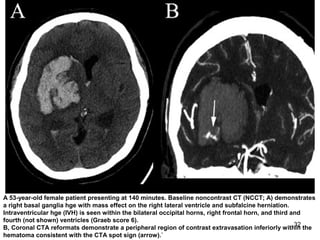

A 53-year-old female patient presenting at 140 minutes. Baseline noncontrast CT (NCCT; A) demonstrates

a right basal ganglia hge with mass effect on the right lateral ventricle and subfalcine herniation.

Intraventricular hge (IVH) is seen within the bilateral occipital horns, right frontal horn, and third and

fourth (not shown) ventricles (Graeb score 6).

B, Coronal CTA reformats demonstrate a peripheral region of contrast extravasation inferiorly within the

hematoma consistent with the CTA spot sign (arrow).`